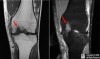

MRI : 박리성 골연골염(Osteochondral Lesion , Osteochondritis Dissecans)